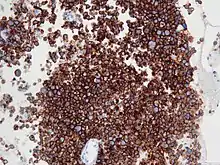

![]() | |

| Micrograph of an anaplastic large-cell lymphoma. H&E stain. | |